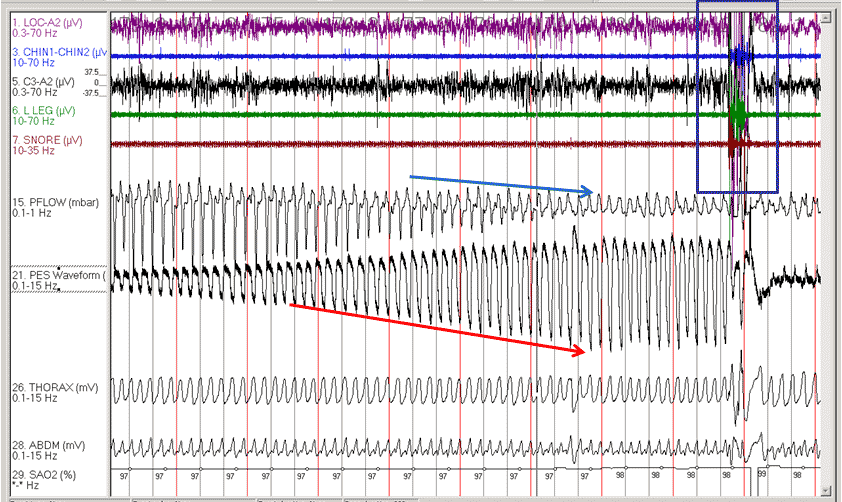

Legend: LOC: left oculogram; CHIN1-CHIN2: chin EMG; C3A2: central EEG leads; LLEG: left leg EMG; SNOR: snoring channel; pFLOW: nasal pressure flow channel; PES Waveform: esophageal pressure trace; THORAX: thorax effort channel; ABDM: abdominal effort channel; SAO2: oxygen saturation channel.

The new AASM scoring manual defines a respiratory effort related arousal as follows: ‘If there is a sequence of breaths lasting at least 10 seconds characterized by increasing respiratory effort or flattening of the nasal pressure waveform, leading to an arousal from sleep when the sequence of breaths does not meet criteria for an apnea or hypopnea.’ The key characteristics are illustrated in the fragment: increasing respiratory effort (red arrow), flattening of the nasal pressure waveform (blue arrow), followed by an arousal (box).

As there is no evidence of desaturation in the fragment, this event does not meet the definition of a hypopnea.